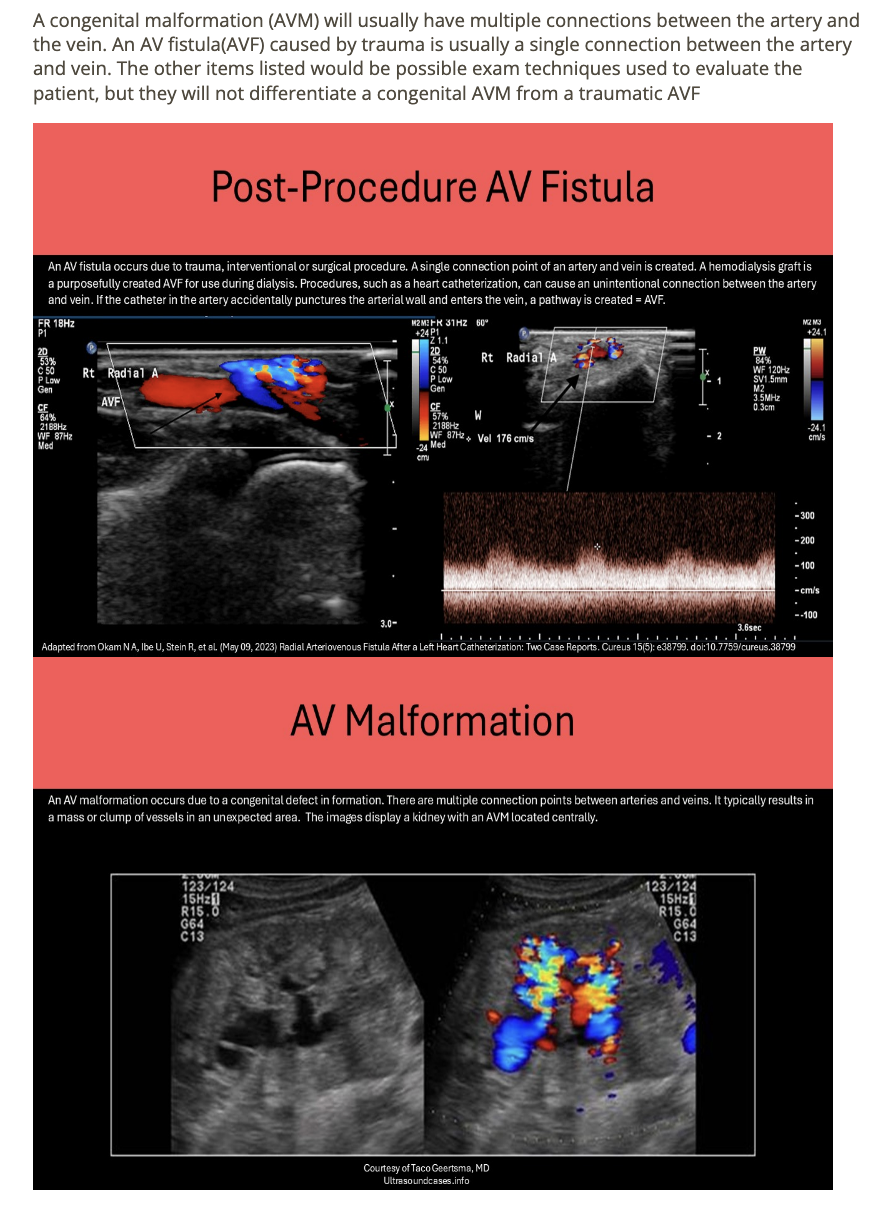

which describes an AV malformation

.

a) dilated venous collaterals adj to AOI

b) can be treated using thrombin injection

c) direct connection between single artery + vein

d) caused by trauma/surgical procedures